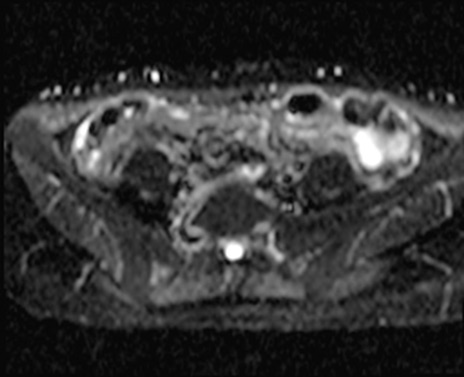

MRI(4日後)